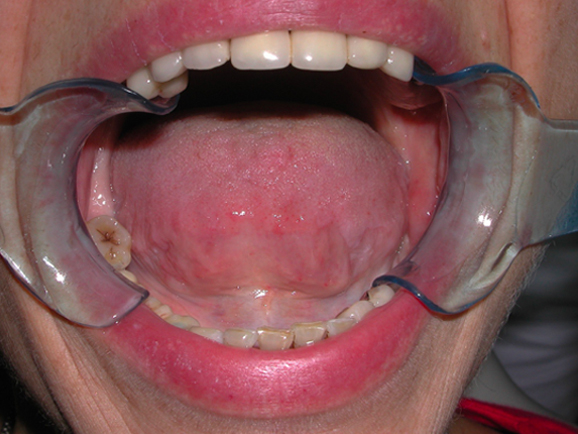

GLI ESITI

Risultati estetici e funzionali conseguiti con la CHIRURGIA RIGENERATIVA